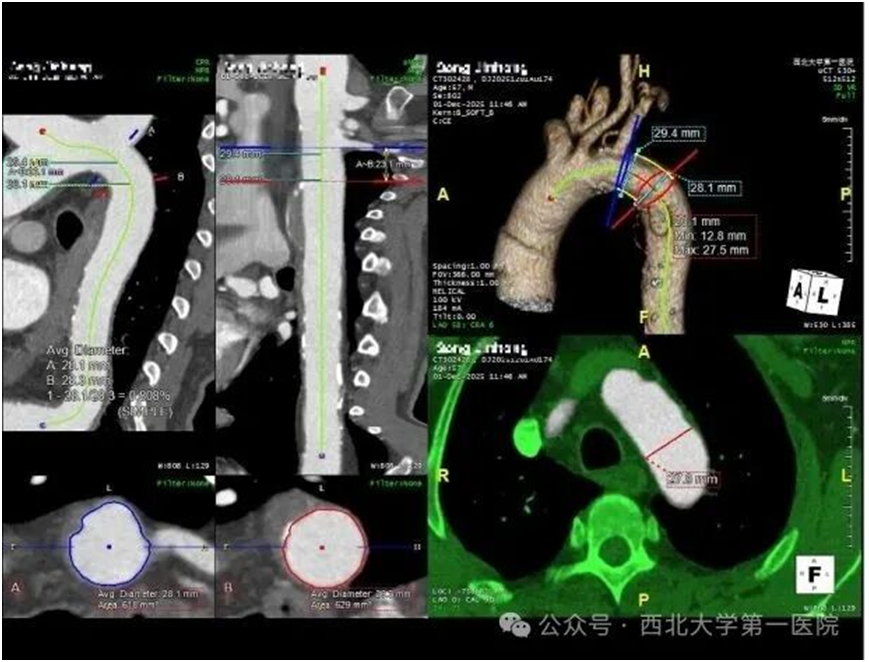

但CTA检查又发现,患者还合并了主动脉穿透性溃疡伴壁内血肿:主动脉壁像破了个“溃疡”,周围积血形成了易破裂的“血泡”,死亡率极高。这就形成了治疗死结:治脑梗需用溶栓、抗血小板药“活血”,却会让主动脉血肿更易出血;防出血要止血、控血压,又会让脑梗血栓更难溶解,加重瘫痪甚至危及生命。

手术无需开胸开腹,仅在大腿根部做几毫米小切口,通过导管将定制覆膜支架送到主动脉溃疡处,精准覆盖破损面,把血肿和血流隔离开。这就像给血管破洞贴了“防水创可贴”,既阻止血肿破裂,又不影响正常血流,创伤小、出血少,术后患者血压稳定,出血风险解除。